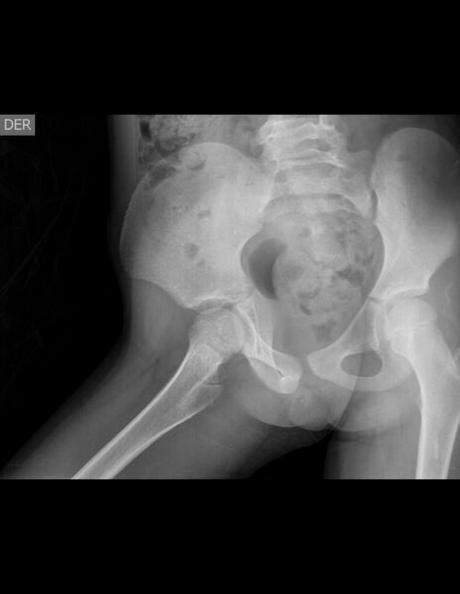

AP Y AXIAL DE PELVIS

HALLAZGOS:

-En lo observado de columna lumbar, central, sin evidencia de lesiones líticas, blásticas o perdidas de la contigüidad.

-Huesos pélvicos y sacro sin evidencia de lesiones líticas, blásticas o perdida de la contigüidad.

-En lo observado de ambos fémures, con adecuada circunferencia cabeza femoral, sin evidencia de lesiones líticas, blásticas o perdida de la contigüidad.

-Espacios articulares observados, con adecuada amplitud.

-Ángulos cervicodiafisiarios, derecho de 148.7° e izquierdo de 143.1°

-Fisis de crecimiento acorde a la edad.

IMPRESIÓN DIAGNOSTICA:

EN EL PRESENTE ESTUDIO DE PELVIS, EXISTE COXA VALGA BILATERAL DE PREDOMINIO DERECHO.

CORRELACIONAR CON DATOS CLÍNICOS Y ANTECEDENTES DE CONSIDERARSE NECESARIO POR MÉDICO TRATANTE, COMPLEMENTAR CON ESTUDIOS ADICIONALES O DE CONTROL, SEGÚN EVOLUCIÓN CLÍNICA DEL PACIENTE.